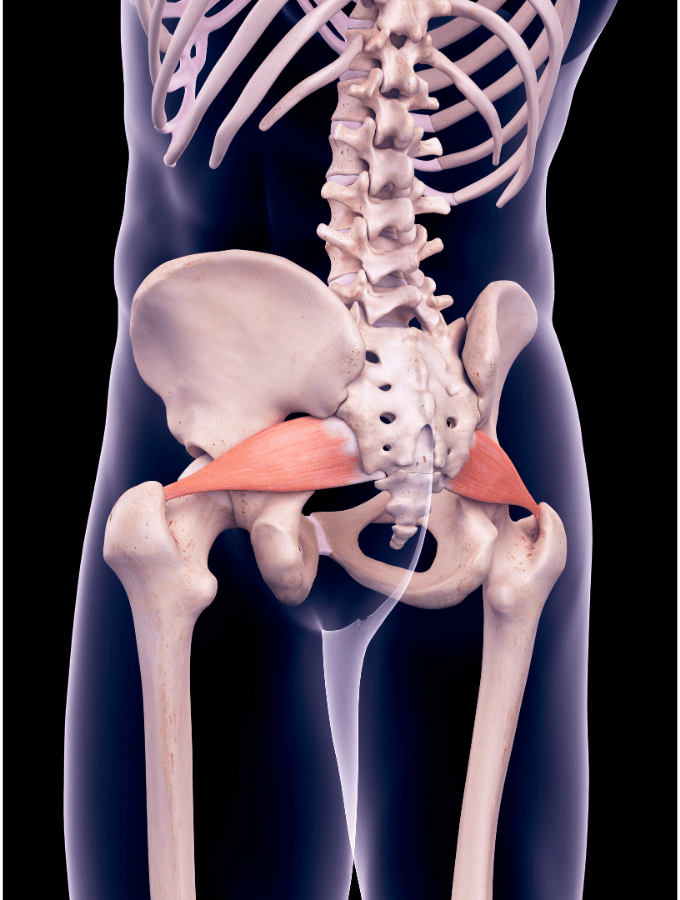

- Kolk

Kaj je išias in 4 uporabni nasveti za odpravo

Išias ali ishiadične bolečine so verjetno najbolj znane bolečine, ki...

Kako za vedno odpraviti bolečine v križu

V tem članku bomo razbili najpogostejše mite o bolečinah v...Izpostavljeno

Kolki: nasveti in vaje za odpravljanje bolečin

Včasih so težave s kolki zelo očitne - bolečine so...